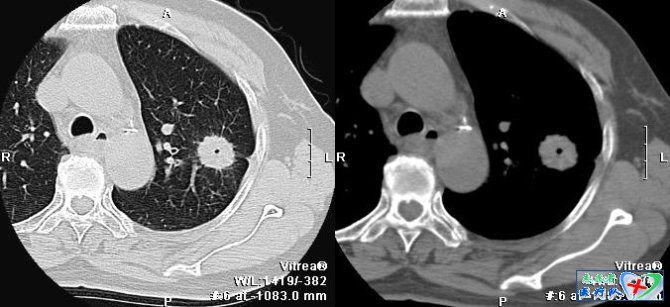

5、CT血管影征(血管包埋征肺静脉包被征)

该征象常用来描述大叶型细支气管肺泡癌(腺癌),是肿瘤沿肺泡壁生长侵润尚未完全破坏肺泡间隔,肺泡壁增厚或邻近肺泡内有分泌物,部分肺泡内仍含气,形成肺炎型改变,增强时可见在病变中穿行的血流强化,称CT血管造影征,多见于肺泡癌。当肺血管进入结节或终止结节时,血管常狭窄。堵塞。截断等。文献认为其中以肺静脉包被(肺静脉包被征)意义最大,提示肺癌机会增加。CT血管影征最初被认为是细支气管肺泡癌的特异性征象(特异性92.3%);而最近这一观点受到怀疑,这可能与缺少明确标准有关(有人提出CT血管影征标准:血管影长>3cm,实变密度低于胸壁肌肉(74HU)。细支气管肺泡癌平均27.6HU,而其它病变73.5HU);CT血管影征见于良性和恶性肺疾病,包括:细支气管肺泡癌、肺炎、肺水肿、中心性肺癌导致的阻塞性肺炎、淋巴瘤及消化道肿瘤肺转移;但在其它病变中实变密度多接近胸壁肌肉。